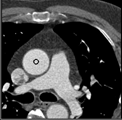

Samples for ascending aorta detection (black circle):

Cluster of candidate points in the ascending aorta.